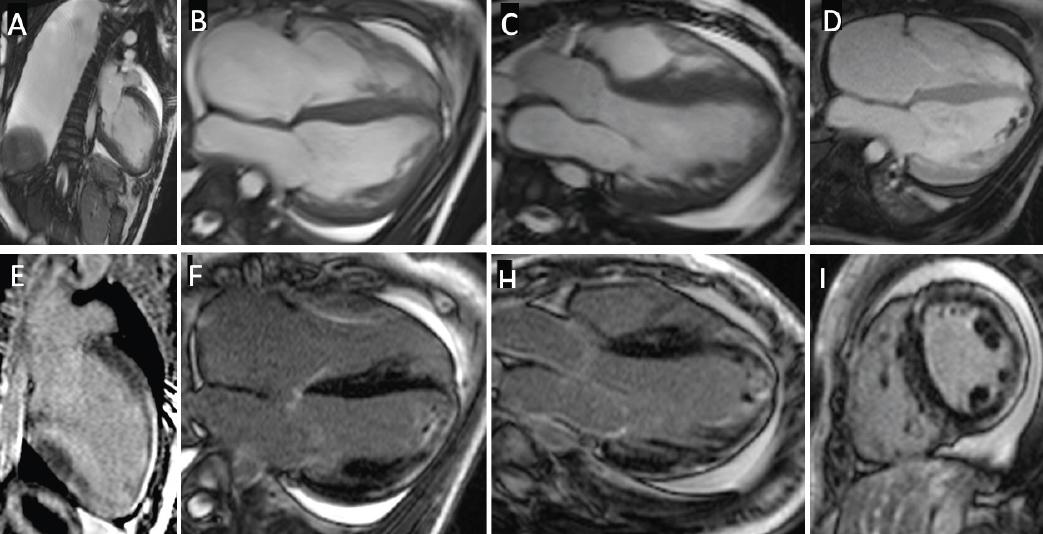

Contrast enhanced cardiovascular magnetic resonance findings. A, B, and C: Diastolic frames of cine images in 2, 4 and 3 chamber views showing a severely dilated left ventricle (LV) with interventricular septum hypertrophy. Large right pleural effusion and small circumferential pericardial effusion are also seen. D: Early Gadolinium enhancement showing multiple thrombi in the LV apex. E, F, G, and I: Late Gadolinium Enhancement (LGE) in 2, 4, 3 chambers and short axis views respectively showing extensive subepicardial LGE with a ring-like pattern.